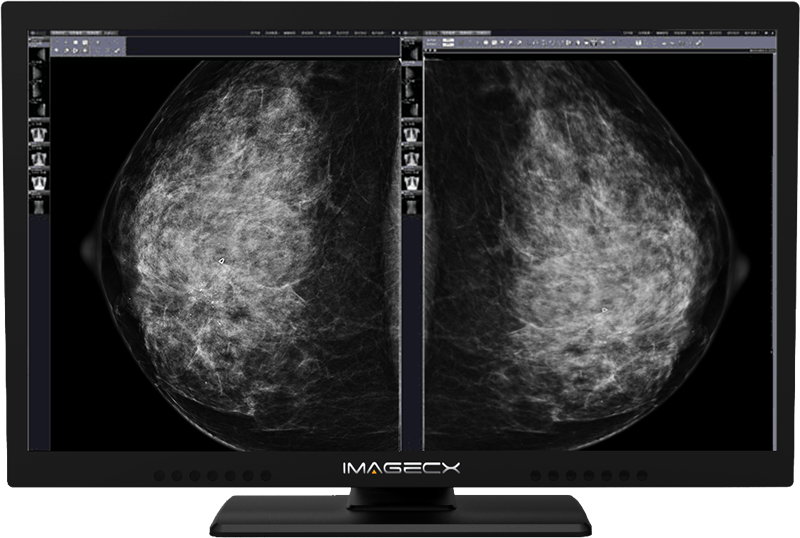

8M一體化雙屏醫用顯示器

產品分類:8MP彩色雙屏醫用顯示器

屏幕尺寸:31.5英寸

分辨率:3840×2160

產品介紹:具有八百萬像素分辨率,超高亮度,超高對比度,寬視角。

在整個壽命期內保持穩定并能夠進行持續的DICOM校準,內置16bit LUT,符合醫療影像高精度需求。

在同一臺顯示器上實現雙屏顯示功能,保證醫療圖像對比一致性,可適用于所有醫療影像顯示,不會成為過渡產品(4K×2K是顯示領域主流)。